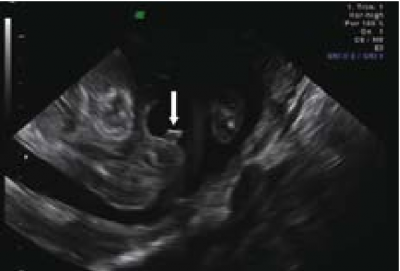

ברונשטיין וחב׳[7] דיווחו שדיוק אבחון מין העובר על ידי אולטרסאונד נרתיקי עולה עם הניסיון, כך שבשנתיים הראשונות לשימוש באולטרסאונד נרתיקי, המין אובחן בדיוק של 76 אחוז ועלה ל-80 אחוז בשנתיים לאחר מכן בין השבועות 14-13 להיריון, ובשבוע 16-15 הדיוק עלה מ-88 אחוז בשנתיים הראשונות לנסיונם ל-96.7 אחוז בשנתיים לאחר מכן. בעבודה זו, מין זכר נקבע על סמך הדגמת מבנה דמוי כיפה (dome sign) המייצג שק אשכים (תמונה 3) בעוד מין נקבה נקבע על סמך הדגמת שניים או ארבעה קווים מקבילים (parallel lines) המייצגים את השפתיים הקטנות והגדולות (תמונה 4) . סימנים סונוגרפיים נוספים בעבודה זו[7] היו הדגמת קו אקוגיני הנמשך מבסיס ועד קצה איבר המין הזכרי ומייצג קו האמצע של הפניס (תמונה 5) וכיוון הפאלוס העוברי (כלפי מעלה מייצג זכר וכלפי מטה נקבה).

אולטרסאונד תלת מימדי - מנסיוננו, שימוש באולטרסאונד תלת מימדי אינו מוסיף משמעותית לאבחון מין העובר, במיוחד בטרימסטר הראשון ותחילת הטרימסטר השני ולעתים יכול אפילו להטעות (תמונה 6). Benoi[9] ואחרים[31], [32] הגיעו למסקנה שאכן התלת מימד אינו עוזר לאבחון מין העובר אך השימוש בחתכים (sectional planes) לעתים יכול לעזור על ידי הצגת החתך הסגיטלי האמצעי ביתר קלות ובכך לעזור לאבחון מין העובר. בטרימסטר השני והשלישי התלת מימד יכול לעזור בהצגת איברי המין להורים בצורה יותר משכנעת (תמונות 7 ו-8). בחלק מהמקרים עם מומים באיברי המין החיצוניים, התלת מימד יכול להדגים את המום ולעזור להגיע לאבחנה, כפי שנדון בהמשך.